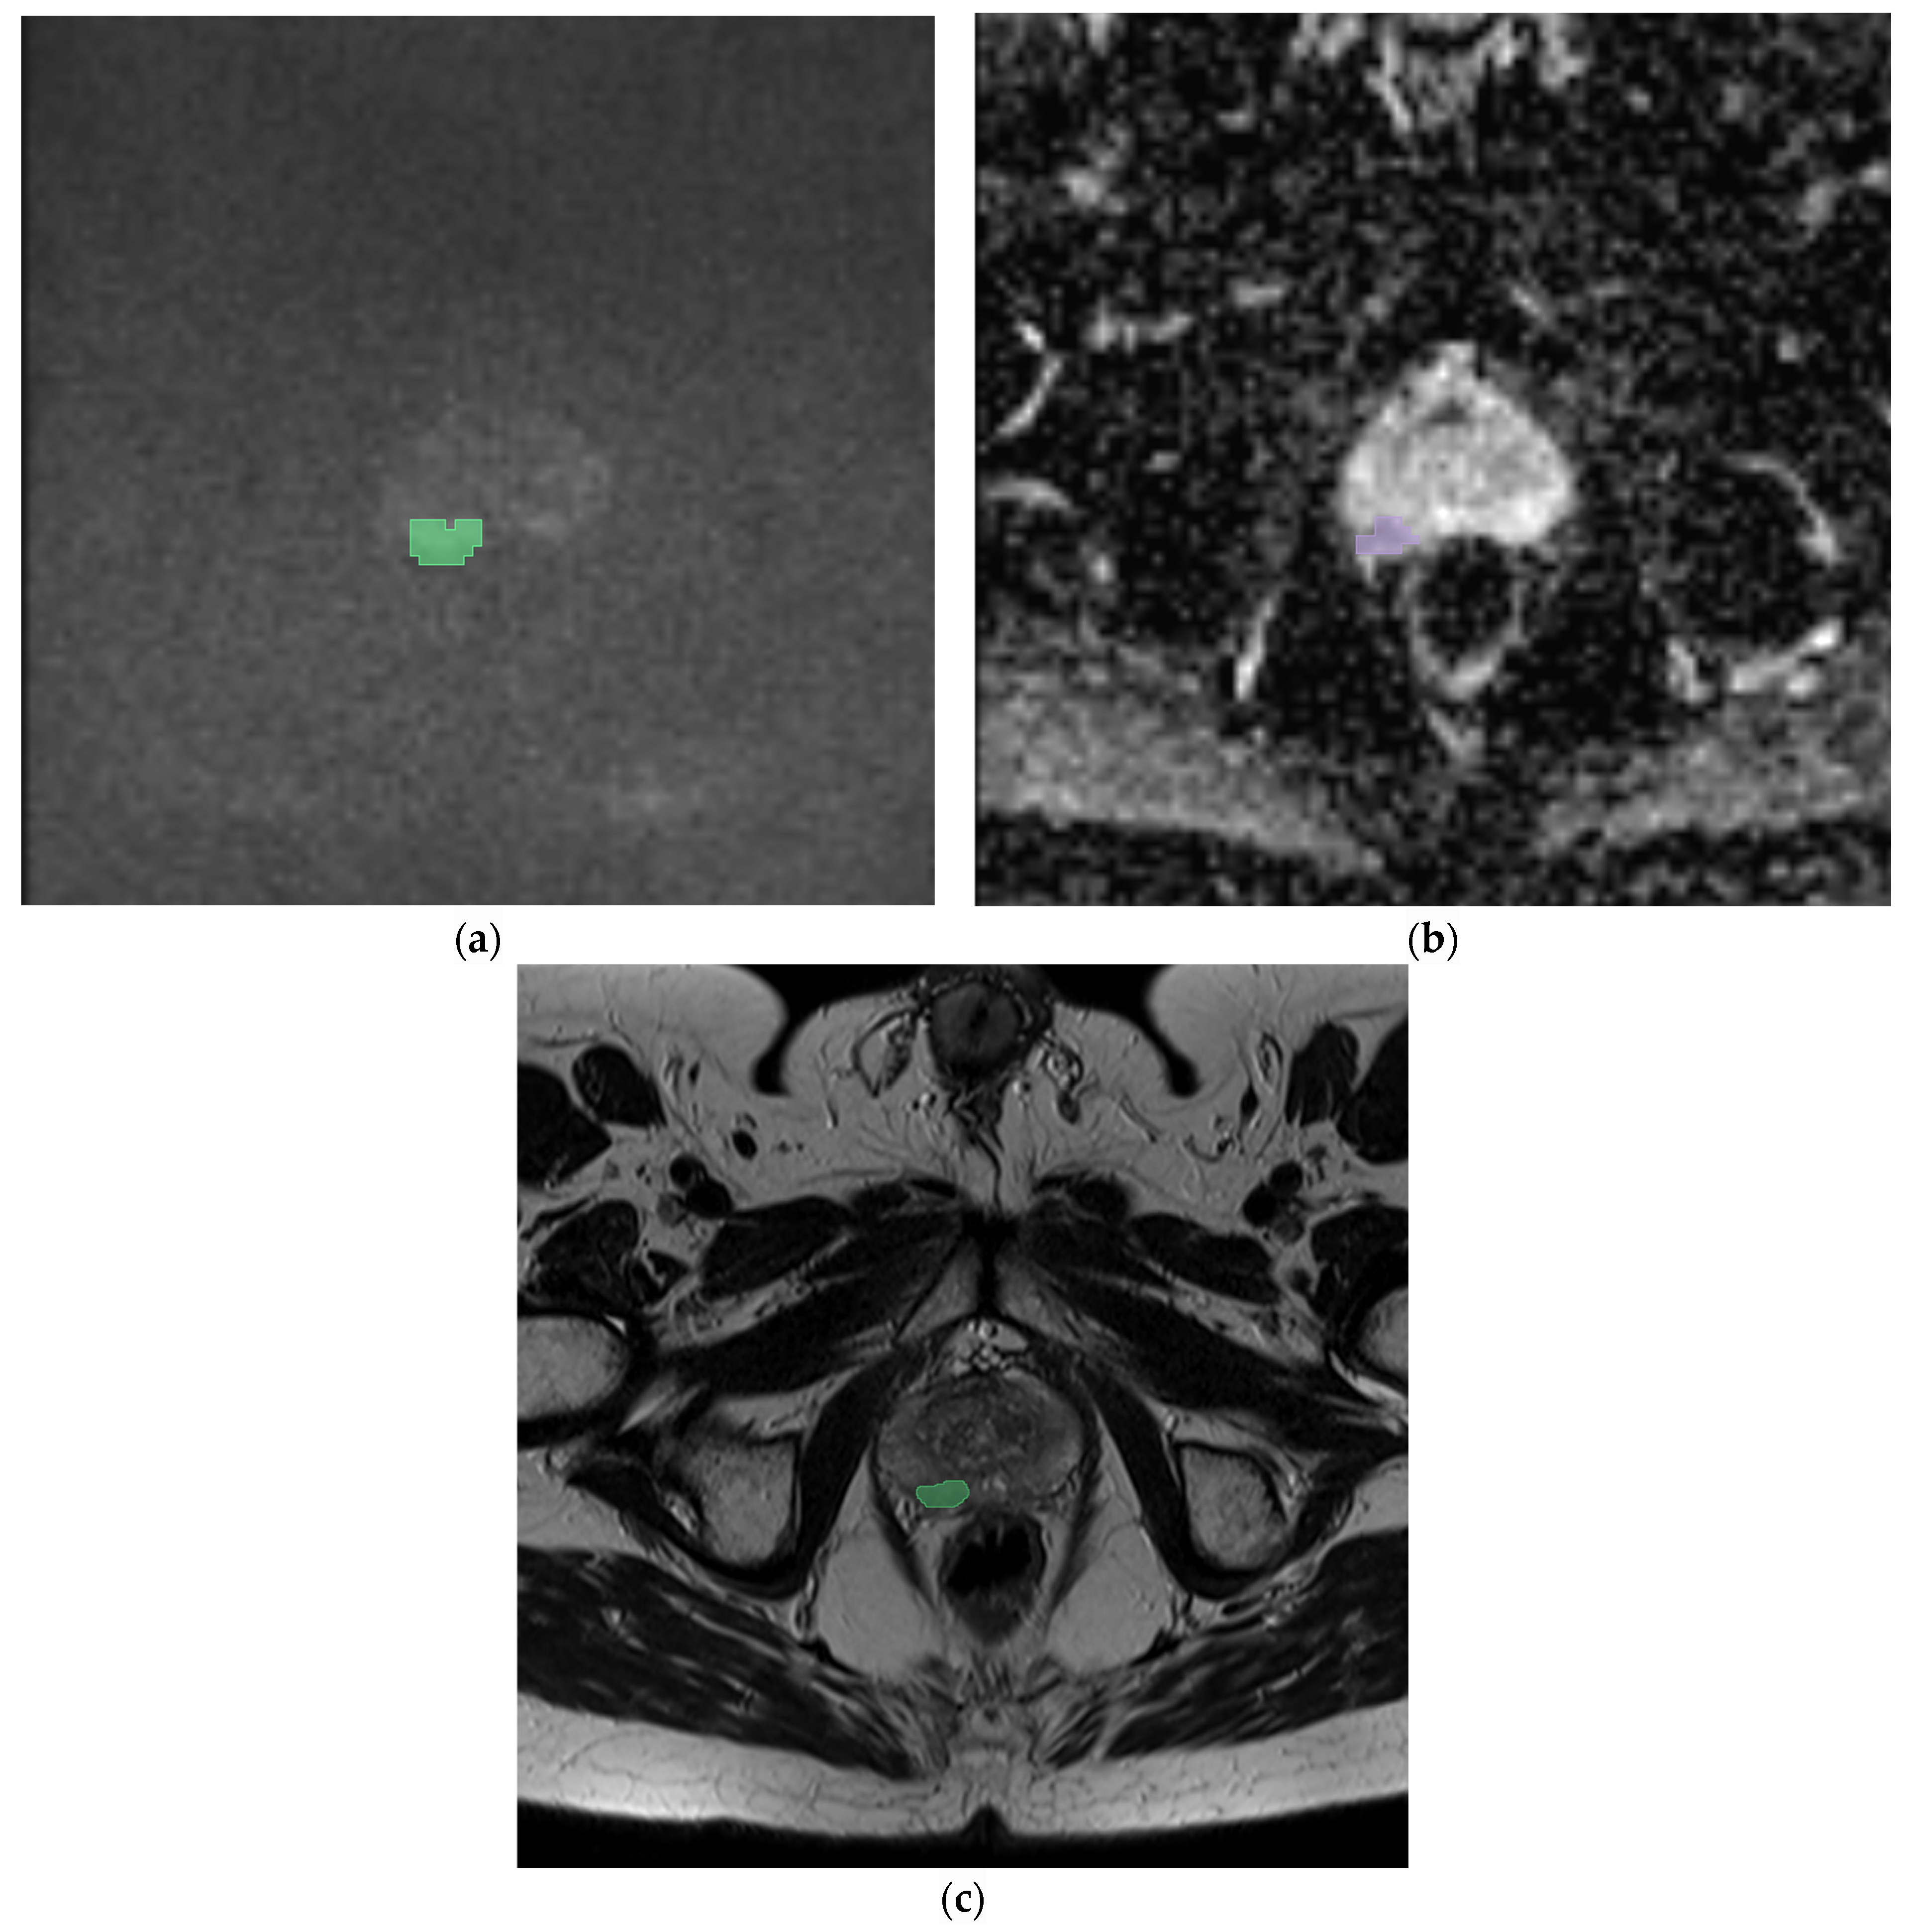

2.2. Segmentation, Feature Extraction